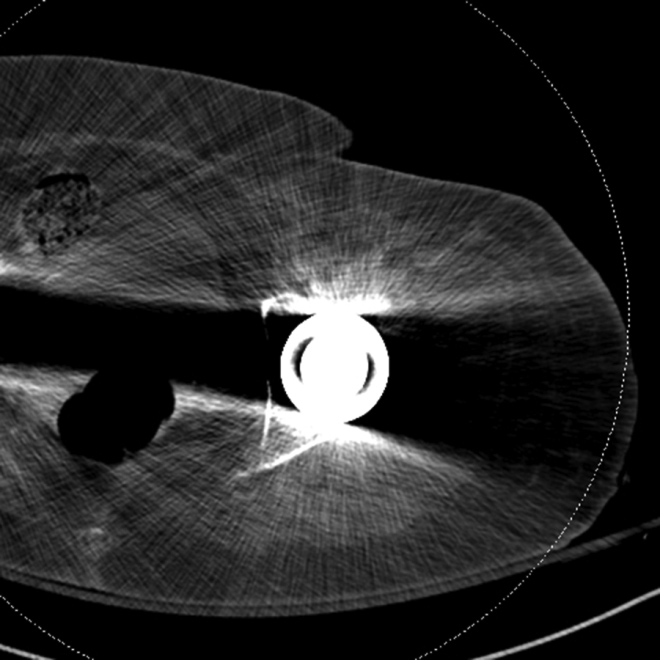

Artifact summation Artifact summation Windowing Windowing

Artifact Summation. (A) Scout image demonstrates bilateral total hip arthroplasties. (B) Axial CT image at the level of acetabular cup and femoral head shows severe transverse streaking related to total summed attenuation of metal components. Optimal Windowing. (A) Axial CT image of the pelvis viewed in soft tissue windows demonstrates extensive streak artifact due to total hip arthroplasty prohibiting evaluation of adjacent bone and soft tissue structure. (B) Same axial CT image set to bone windows results in improved visibility of adjacent bone and soft tissue anatomy.